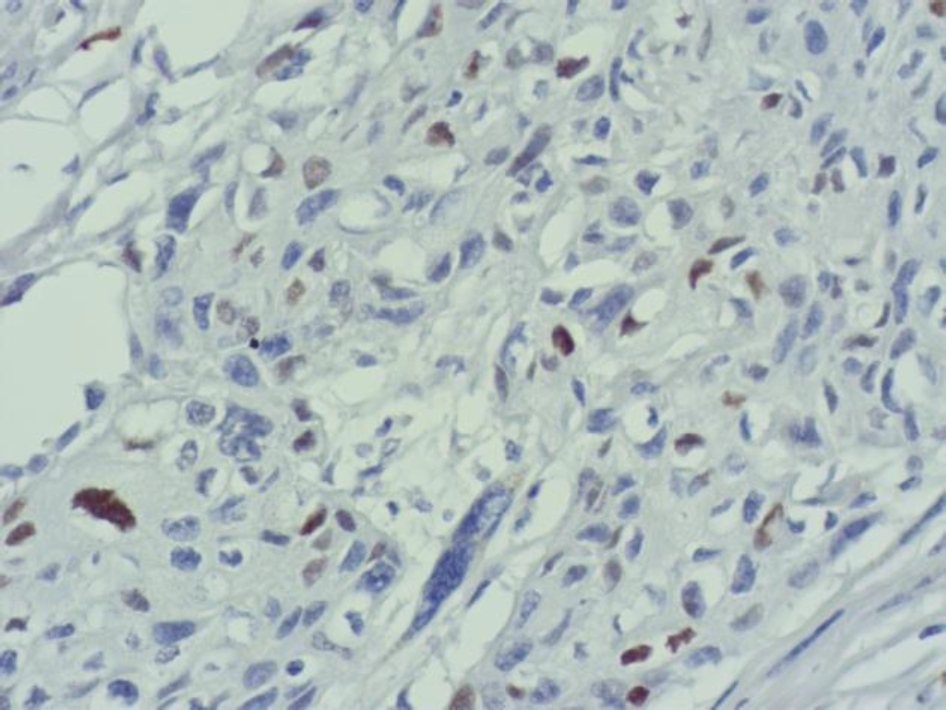

Во всех 19 исследуемых наблюдениях проведено дополнительное параллельное иммуногистохимическое исследование по выявлению экспрессии белков EGFR и Cyclin D1 соответственно, при этом диффузная, преимущественно умеренная экспрессия EGFR опреде-лялась в 17 (89 %) из 19 наблюдений (рис. 3), очаговая слабая экспрессия – в двух наблюдениях (11 %).

Экспрессия Cyclin D1 всех анализируемых наблюдений была очаговой, слабой и умеренной (рис. 4).

Рис. 3. Диффузная экспрессия EGFR в клетках плоскоклеточного рака языка. ИГХ окрашивание, ×100

Рис. 4. Очаговая слабая и умеренная экспрессия Cyclin D1 в клетках плоскоклеточного рака языка. ИГХ окрашивание, ×400

В нашем исследовании в 100 % наблюдений с амплификацией гена EGFR выявлена экспрессия белка EGFR, однако в 89 % экспрессия была сильной, а в 11 % наблюдений – умеренной. Исследователями также в 100 % наблюдений рака языка выявлено соответствие между амплификацией гена EGFR и экспрессией белка EGFR, однако наблюдения с высоким количеством копий EGFR сопровождались более интенсивной экспрессией белка EGFR при иммуногистохимическом исследовании. Мы не выявили такой закономерности.

Количество опухолевых клеток с амплификацией гена CCND1 в наших наблюдениях составило от 1 до 87, при этом гиперэкспрессии белка Cyclin D1 не определялось, экспрессия была очаговой, слабой и умеренной. По данным исследователей амплификация протоонкогена CCND1 при раке ротовой полости зависит от локализации, в частности, при раке языка составляет 88 [11] и 56,5 % [12], при плоскоклеточном раке щеки – 56 % [11], однако количество клеток с амплификацией не изучалось. В случаях разных категорий и степеней опухолевой дифференцировки определялась очаговая, слабая и умеренная экспрессия белка Cyclin D1, независимо от количества клеток с амплификацией протоонкогена CCND1. В работе исследователей также отсутствовала корреляционная связь между амплификацией CCND1 и экспрессией белка Cyclin D1 в случае плоскоклеточном раке полости рта [13].